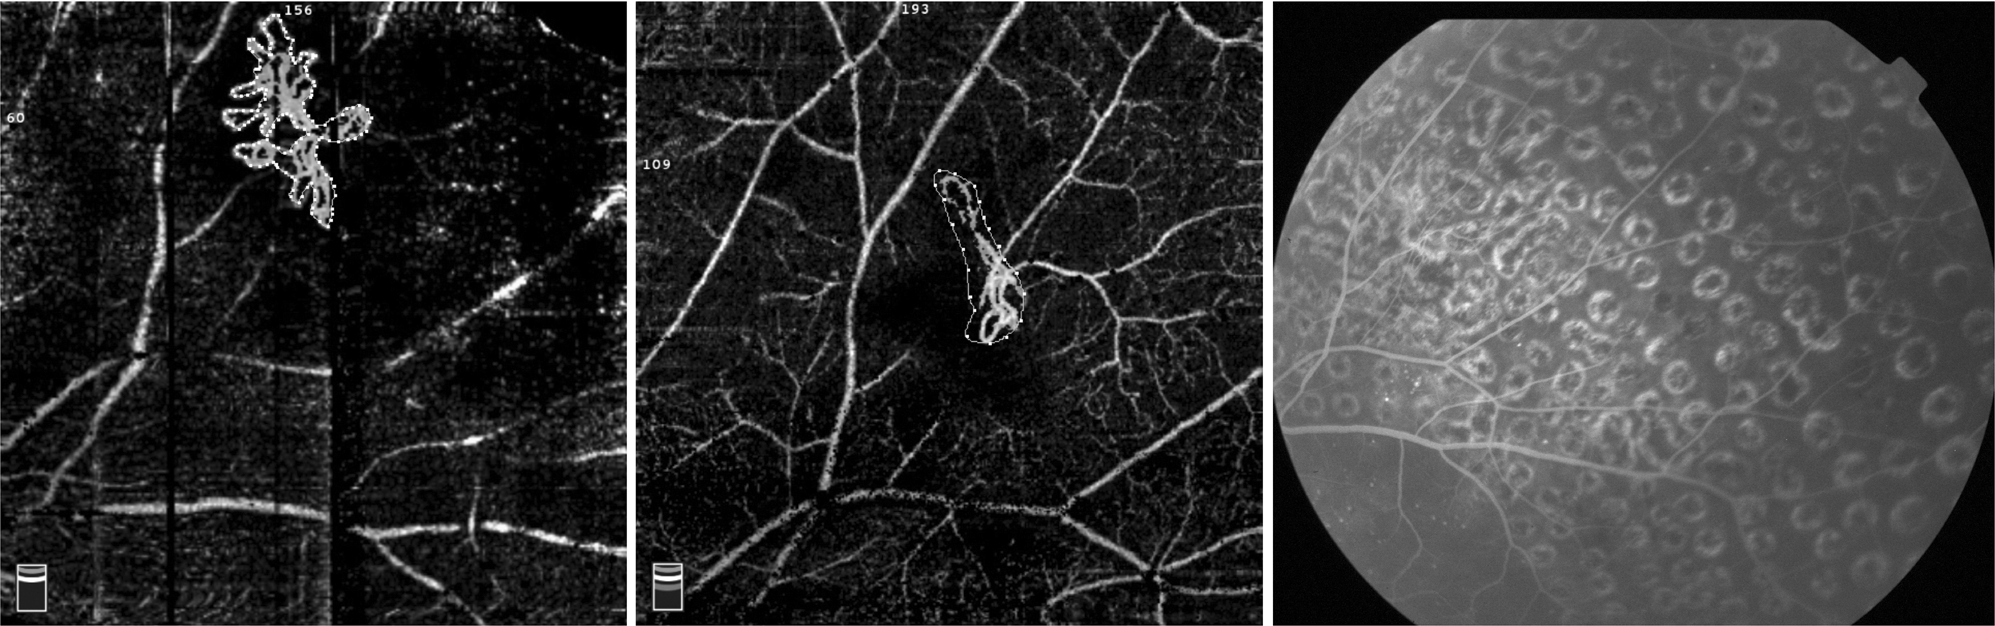

Fig. 4

Neovascularization at baseline OCTA with an area of 0.653 mm2 (left); OCTA still showed abnormal vascular shape at an interval of 1 year after PRP, with an area of 0.272 mm2 (middle), and no evidence of fluorescein leakage was seen at the FFA (right)